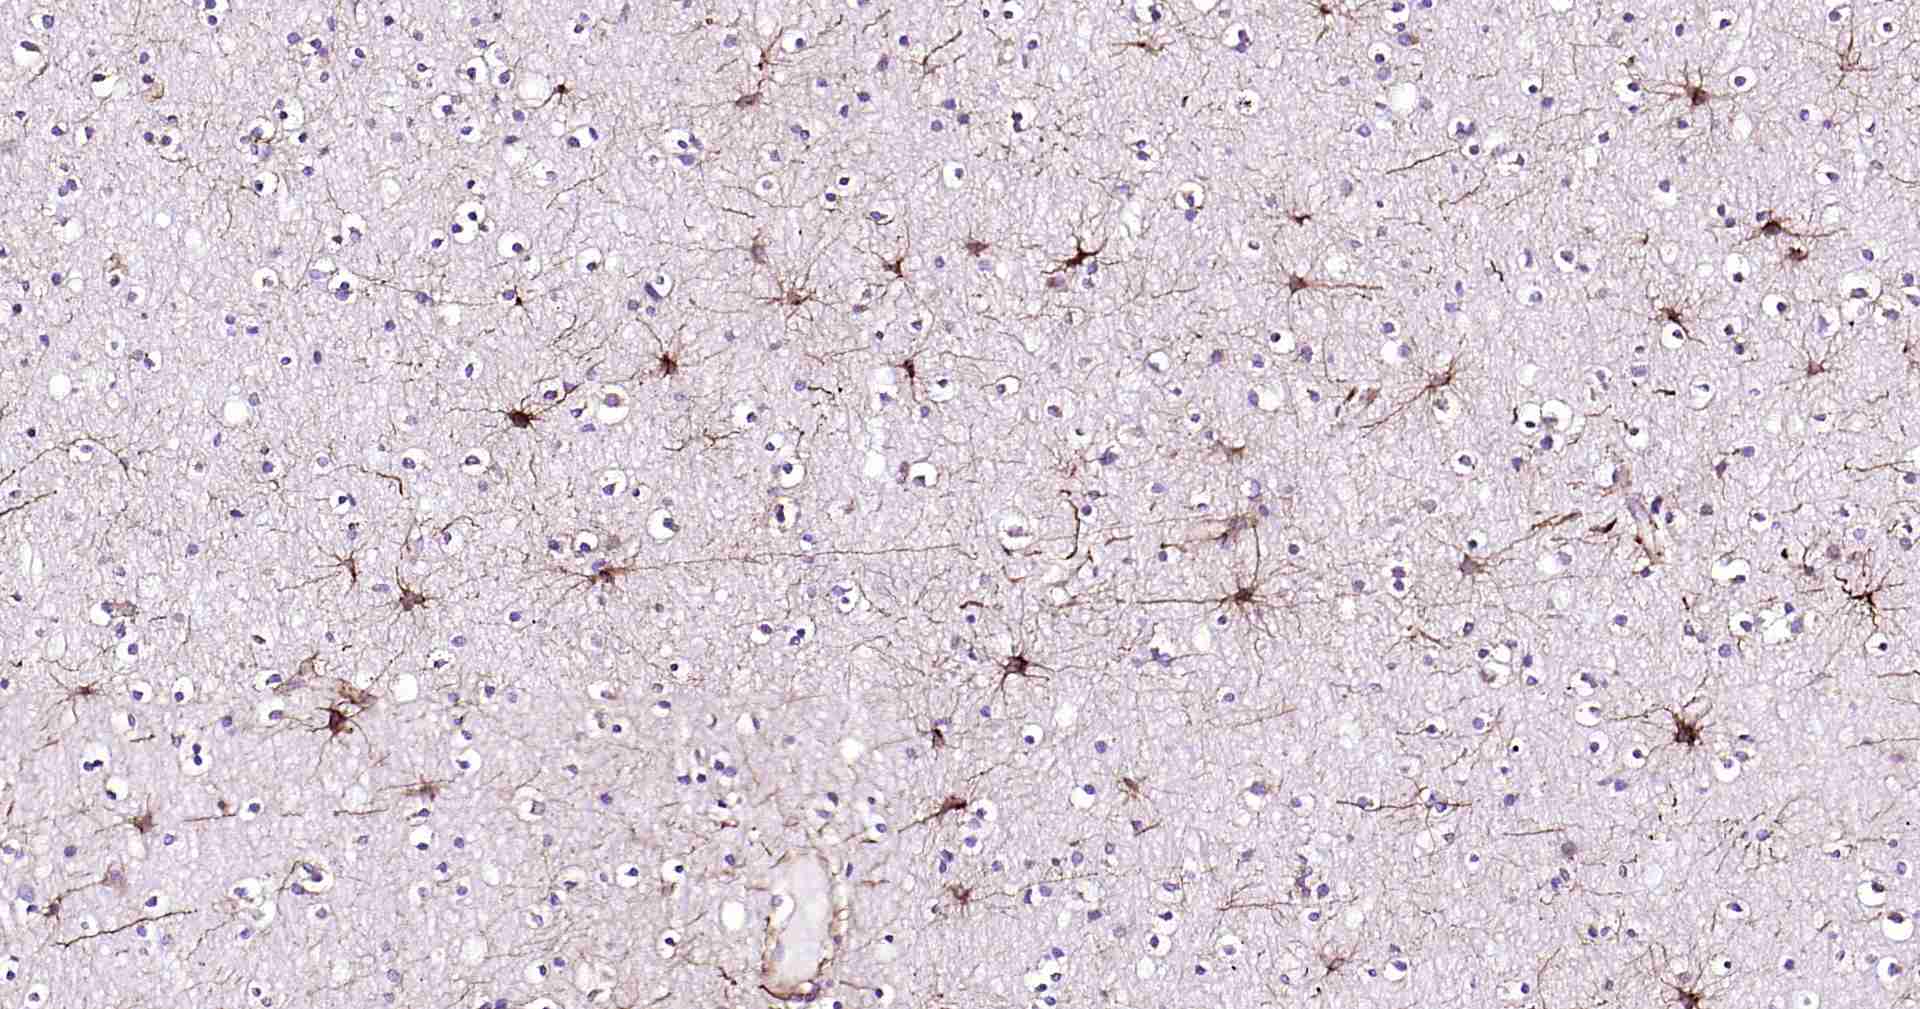

Bioss推出的系列超敏二步法免疫组化检测试剂,它将多聚辣根酶复合物(Polymer-HRP)和二抗抗体分子聚合在一起,替代传统方法中的二抗和三抗,直接放大抗原抗体结合的信号,既保留了抗体特异性结合抗原的能力,又可有效的避免聚合分子过大而造成的空间位阻。此试剂盒与传统的SP三步法相比,具有简单、快速、敏感等特点,因为系统中不再使用生物素,所以避免了由于内源性生物素所造成的背景染色。本品独特的Polymer-HRP有利于大分子的检测系统更好的结合所检测的一抗分子,此检测系统是目前已知的灵敏度最高的系列免疫组化检测系统。

此外,本试剂盒还提供了内源性过氧化物酶阻断剂工作液,可抑制内源性过氧化物酶的活性,达到降低背景染色的目的;另提供了正常山羊血清封闭工作液,因二抗可能会与组织中的内源性免疫球蛋白发生交叉反应,使用二抗宿主来源的非免疫血清预处理该组织,可最大程度减弱此反应。

7、使用DAB显色液显色,蒸馏水清洗切片以终止反应。

8、如果需要,可进行苏木素复染、脱水、透明、封片、镜检。